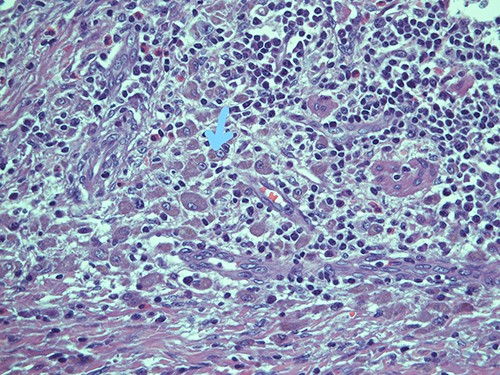

On microscopy, the appendix showed a thickening of his walls due to an accumulation of rounded elements with rich granular cytoplasm containing amorphous corpuscles and surrounded by microcalcifications, macrophage elements with adjacent de-epithelialized, ulcerated and eroded mucous tracts. No positive S100/pancytokeratin elements were found in the numerous sections examined. The morphological findings therefore indicated a form of malakoplakia (Figs 1–3), confirming its non-eptheliod and non-neoplastic nature (Fig. 4).

Submucosa is expanded and colonized by a dense histiocytic population (von Hansemann cells) and harboring microcalcifications; haematoxylin and eosin, magnification ×20.